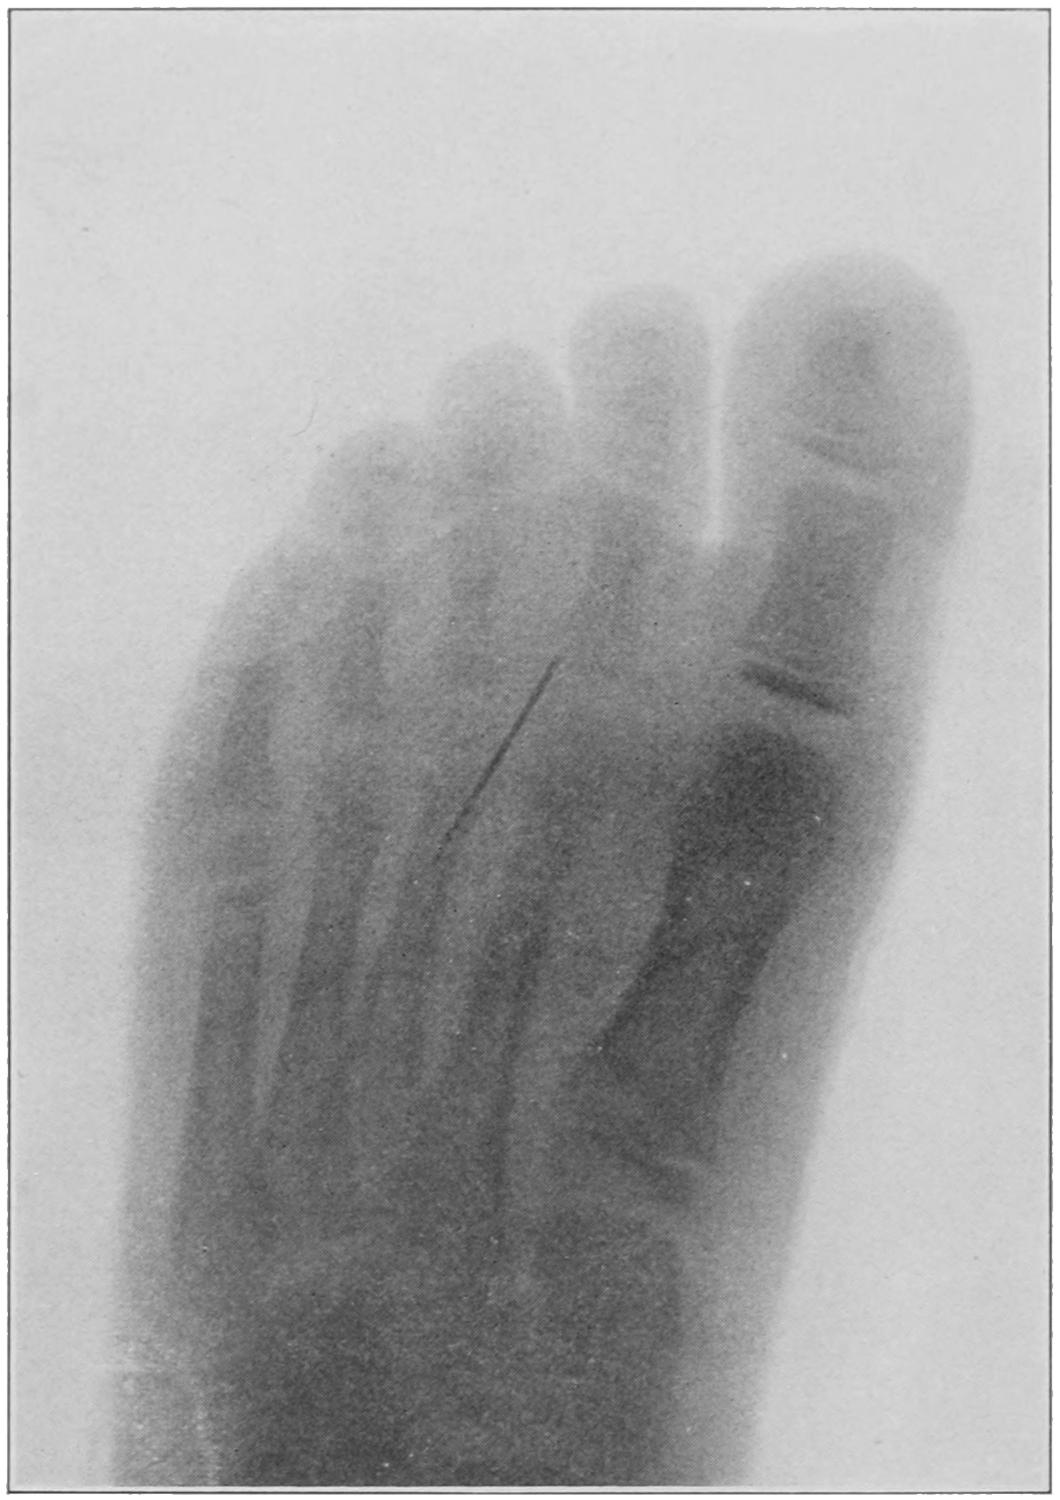

Fig. 1

Congenital hypertrophy: gigantism of both lower extremities. (Case of Dr. Graefe [Sandusky].)